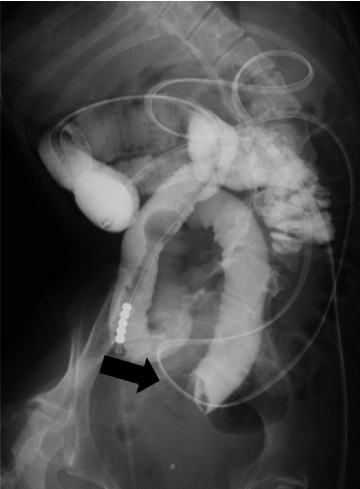

Gallstone ileus is an uncommon complication of cholelithiasis and the delayed diagnosis may be associated with increased risk of mortality. When gallstones block the cystic duct, they can lead to cholecystitis. If a fistula forms between the inflamed gallbladder and the adjacent intestine, the gallstones may pass into the intestinal tract and cause obstruction in the intestine. We report a case of 25-year-old female with developmental and epileptic encephalopathy who was intraoperatively diagnosed with gallstone ileus during surgery for small bowel obstruction of unknown origin. The patient had potential risk factors enhancing the formation of cholesterol gallstones, including long-term use of phenobarbital, vagus nerve injury in open gastrostomy and laparoscopic fundoplication, and tube feeding; however, the patient's gallstone had been undiagnosed for a long time. Computed tomography of the abdomen showed small bowel obstruction and pneumobilia. The presence of pneumobilia in a patient without a surgical history of the biliary system should raise suspicion of a bilioenteric fistula. The awareness of this complication of cholelithiasis is important to make an early diagnosis and to initiate the appropriate treatment.

Abstract Image